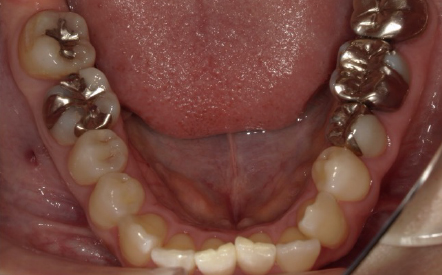

「入れた被せものの色が気になる 過去銀歯による治療を受けてきたが、再発を繰り返している。

見た目も気になるのでしっかり治したい」

→全顎的に補綴物の不適多数。多数歯に2次カリエス(虫歯)。咬合も不正。

Before

30代女性 治療期間:2か月半 費用:168万円 (税込)

■ 治療計画

全顎的に不良補綴物(被せもの)を除去し、ジルコニアにて補綴物を新製。

■ 経過

全顎的に不良補綴物を外し、カリエス(虫歯)を除去。中心位(顎関節による決定する顎位)にて咬合採得を行い、ジルコニアにて修復を行いました。現在、咬合、機能、審美、ともに全く問題なく経過しています。